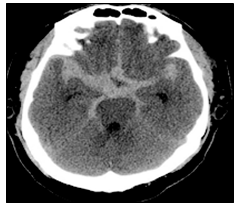

[응급처치학개론] 40대 여자가 갑자기 벼락 치듯 심한 두통과 의식저하로 응급실에 내원하였다. 뇌 CT 영상이 다음과 같을 때 진단으로 옳은 것은?

- ③ 지주막하출혈